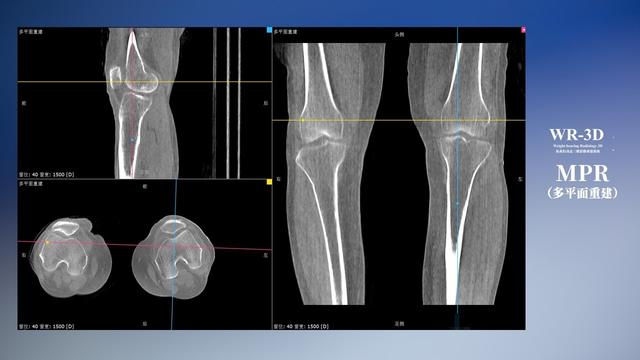

与此同时,数字化X线摄影技术相较于CTMRI来说,能快速获取真实、直观、满足临床需要的影像。DR的图像具有图像层次丰富、空间分辨力高、影像边缘锐利清晰、密度分辨力高级细微结构表现出色等特点,针对膝关节解剖结构数字化X线摄影技术应用价值很高,尤其是是对骨小梁与骨皮质的显示非常清楚。在负重位状态下,数字化X线三维摄影扫描与重建,能够更好的呈现受检者关节受力改变的状态。ty8天游平台登录科技创新的WR-3D动态三维数字化X线摄影技术,通过数字化X线摄影完成三维扫描并重建三维影像信息,包括MPR多平面重建、MIP重建以及VR绘制。扫描时间短,剂量相较于CT设备大幅缩减,同时成本更低,在临床诊断以及医疗方案制定中具有极大的价值意义。相较于普通平片下的负重位扫描,负重位动态三维扫描摄影技术能够避免二维状态下的组织结构重叠、密度分辨率不足、组织解剖结构难以分辨等问题,WR-3D支持多角度的动态三维摄影观察,能全面的呈现被检查部位在多个角度下三维影像信息,极大的减少了二维负重位检查的漏诊率。

ty8天游平台登录科技WR-3D负重位动态三维摄影技术